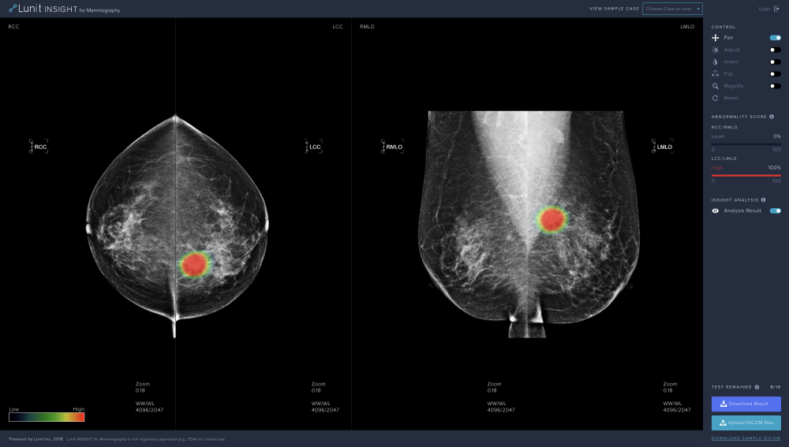

의료 인공지능 기업 루닛은 유방촬영술을 위한 인공지능 소프트웨어 루닛 인사이트(Lunit INSIGHT for Mammography)를 공개했다. 루닛 인사이트는 97%의 정확도로 유방암을 발견하는 의료 인공지능 소프트웨어로 촬영된 영상 이미지를 업로드하면 종양의 위치는 히트맵으로, 종양의 악성 정도는 점수로 즉각 표기된다.

루닛은 임상 연구 결과 루닛 인사이트가 영상의학과 전문의의 판독 성능에 긍정적인 영향을 보여줄 수 있을 것으로 내다보고 있다. 루닛 서범석 대표는 “전 세계적으로 암의 25%가량이 유방암이지만 유방촬영술의 판독 정확도는 32%로 매우 낮다”며 “루닛 인사이트를 활용하면 영상의학과 전문의의 판독 정확도(detection rate)는 증가하고 재검률(recall rate)은 줄어들 것으로 기대된다”고 밝혔다.